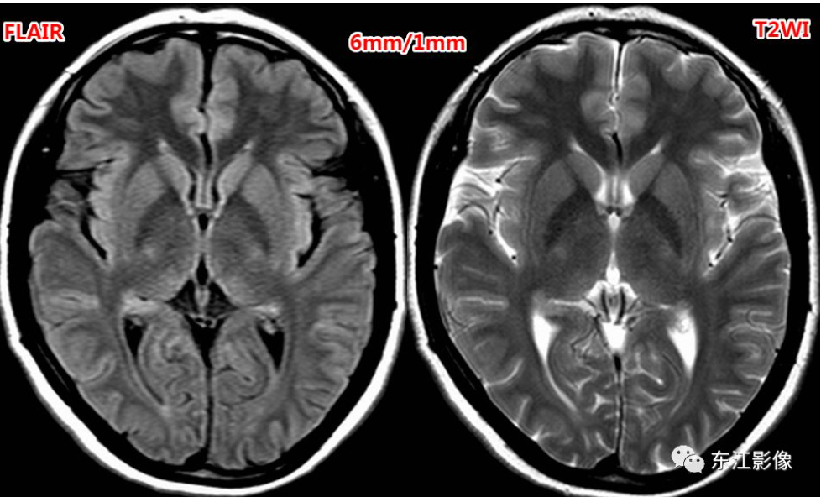

3、压水FLAIR